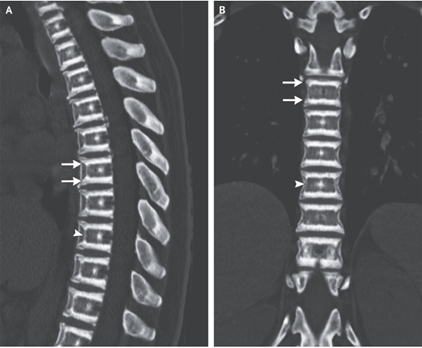

60歳男性。強直性脊椎炎の病歴をもつ。 転倒後、首の痛みと腕と足の麻痺が出現し、頸椎カラーをつけて救急搬送となった。 ここ5年間強直性脊椎炎の治療を自己中断して…